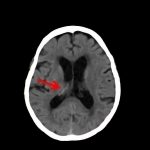

断層撮影

手術前1